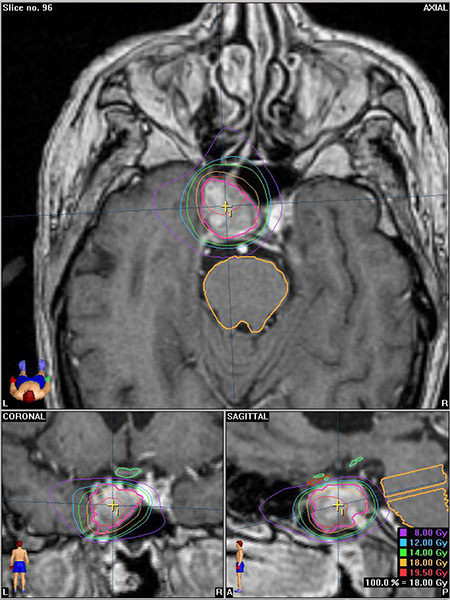

.

Casos Neuroloquirúrgicos

Envíado por Dr. Ruben Eduardo Amaya Contreras